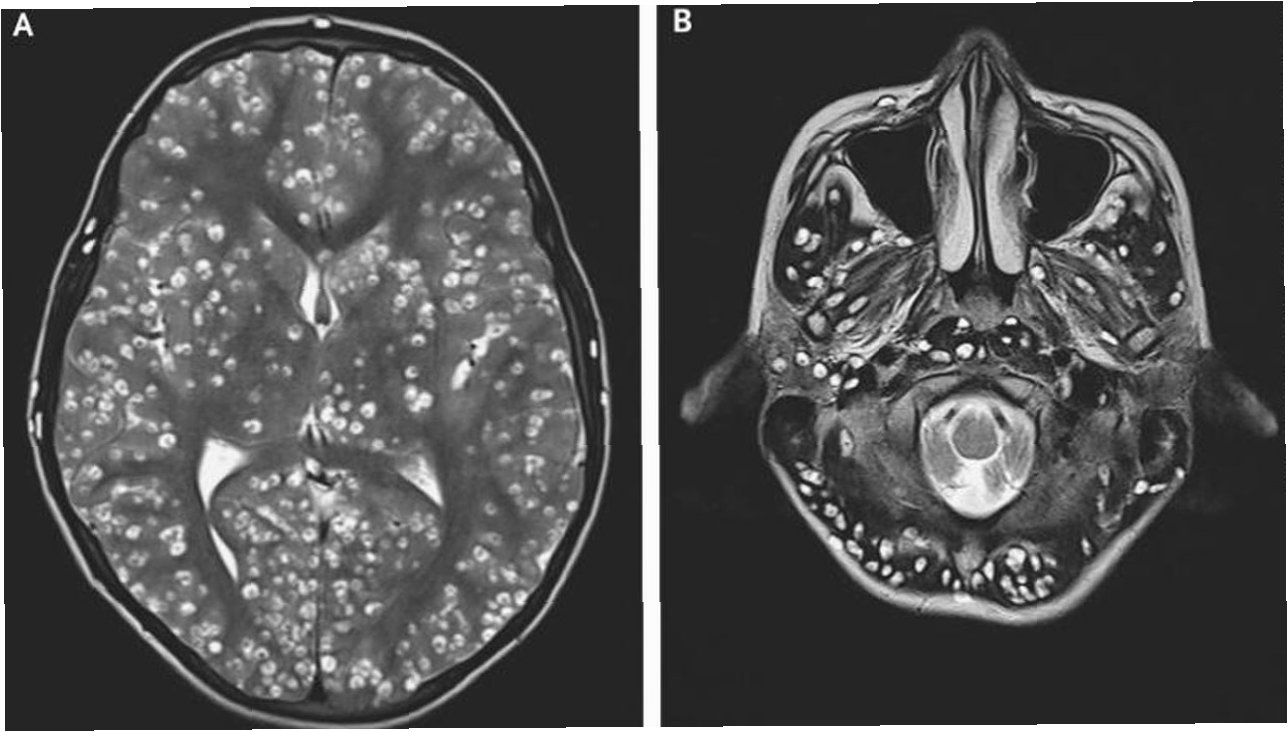

인간 최초! 뇌에서 꿈틀댄 기생충의 충격적 실체와 감염 경로

야생 채소 섭취 후 발생한 희귀 기생충 감염호주에서 60대 여성이 집 주변 야생 채소를 먹은 후 희귀 기생충에 감염된 사례가 보고되었습니다. 이 여성은 3주간의 복통, 설사, 마른기침, 야간 발한 증상을 겪었으며, 폐와 간, 비장에서도 손상된 조직이 발견되었습니다. 초기에는 호산구성 폐렴으로 진단받았으나, 스테로이드 치료에도 불구하고 증상이 호전되지 않아 추가적인 검사가 진행되었습니다. 이 사례는 인간에게서 처음으로 확인된 '오피다스카리스 로베르치'라는 기생충에 의한 감염으로 밝혀져 학계의 큰 관심을 받고 있습니다. 진단과 치료의 어려움, 그리고 뇌 침투환자는 여러 검사에도 불구하고 기생충 감염의 명확한 흔적을 찾기 어려웠습니다. 세균, 곰팡이, 기생충 항체 검사 등에서 음성 반응이 나왔고, 구충제..